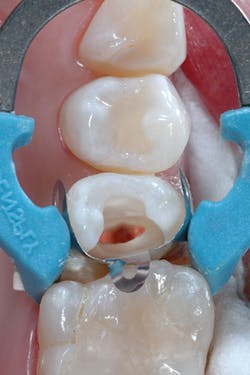

A 20-year-old female patient presented for a core buildup on tooth No. 4 following unremarkable root canal therapy. The tooth was isolated with a Palodent Plus Sectional Matrix System, and Prime&Bond Elect Universal Adhesive (Dentsply Sirona) was applied per manufacturer’s directions (figure 2). An initial 1 mm layer of SureFil SDR flow+ universal shade was placed over the gutta percha and light cured.